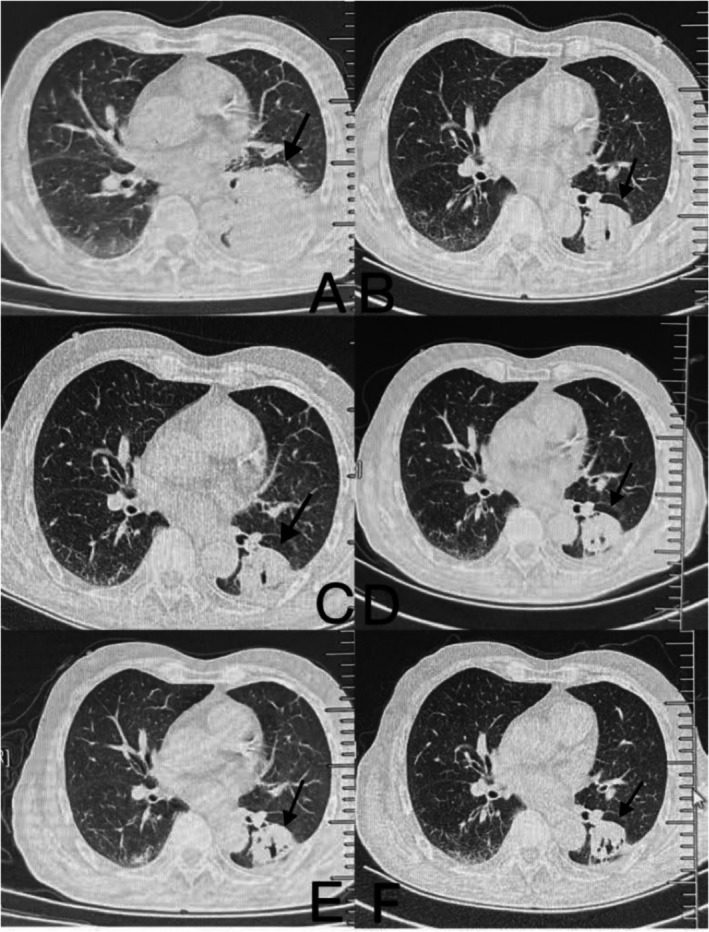

Case presentation: We present the case of an 83-year-old patient with stage IV lung adenocarcinoma treated with four cycles of intravenous Tirelizumab and two cycles of intratumoral Tirelizumab via tracheoscopy. The patient achieved partial clinical remission, with tumor lesions continuing to shrink upon follow-up by August 24, 2024. No treatment-related adverse reactions were observed, and the patient's immune function remained normal.